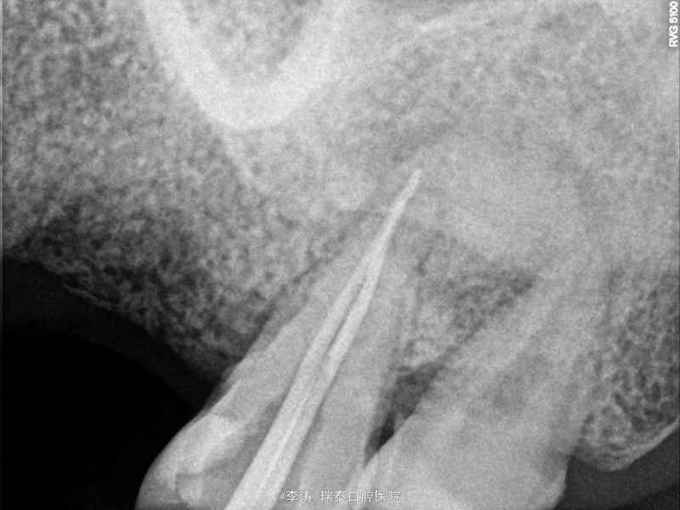

牙骨质瘤 牙骨质瘤

26残冠 25,27根管治疗不到位 27牙根尖区高密度影 所有牙均无临床症状

经多方会诊,确认考虑27牙根尖牙骨质瘤,建议先行根管治疗,然后密切观察 予以拔除26,根管治疗25,27

几个问题 1,26牙修复方式是种植还是烤瓷桥,26如果种植,成功的几率大不大 2,27牙的预后会是怎么样,见得不多,望请赐教